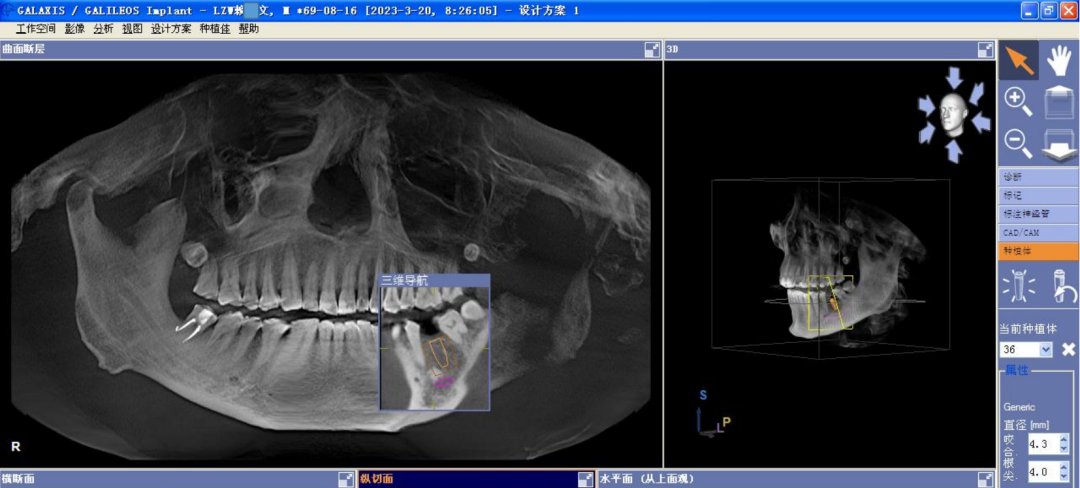

颊舌向宽度约7-8mm,骨质正常,无疏松影,35根尖远中见一"骨岛"影像